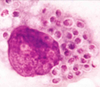

An immunocompromised patient presents with “soap bubble” lesions in his brain on imaging. How does an infection with Cryptococcus neoformans lead to this?

Through hematogenous dissemination after inhalation

A male patient, positive for HIV, has an infection with a heavily encapsulated, nondimorphic yeast. What is the likely diagnosis?

Cryptococcus infection

You culture Cryptococcus neoformans at 25°C and then at 37°C. What morphology do you note?

C neoformans grows as a yeast at both temperatures (it is not dimorphic)